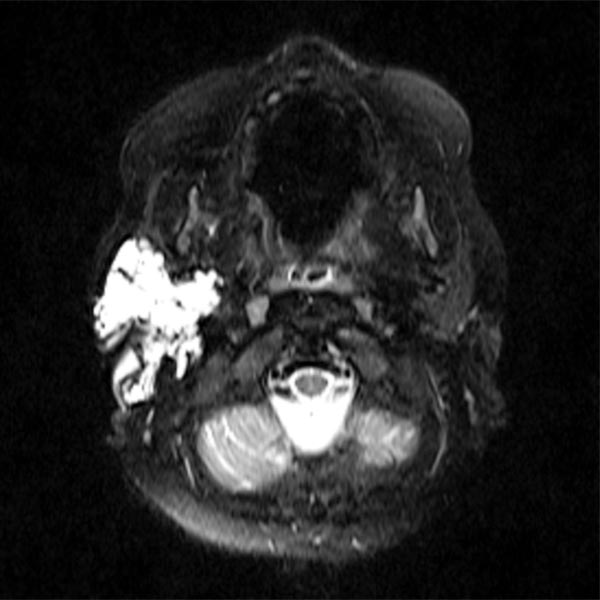

Transversales, T2-gewichtetes, fettgesättigtes MRT 13 Monate nach der OP. Nur wenige Reste der LM sind noch sichtbar.